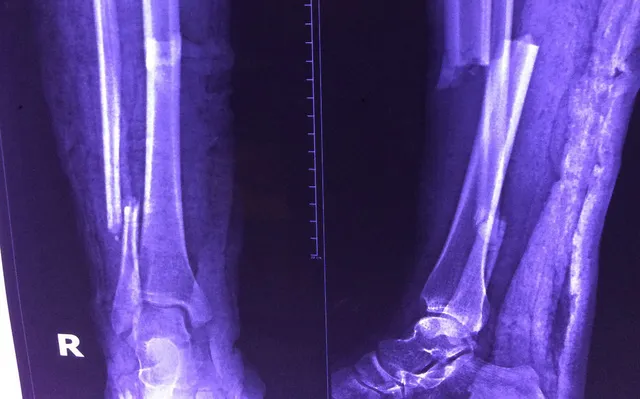

X-quang kiểm tra xương gãy của bệnh nhân.

Các BS ghi nhận chị D. bị gãy xương cẳng chân bên phải (đoạn ống quyển) thành hai đoạn phức tạp. Ca mổ khá nguy hiểm vì chỉ cần đi một bước lên cầu thang bệnh nhân đã khó thở, tím tái. Ca mổ ghép xương không khó nhưng bệnh nhân mắc bệnh tim bẩm sinh, nếu gây tê toàn thân máu đổ về tim nhiều sẽ khiến tim quá tải, hết sức nguy hiểm. Vì vậy, bệnh nhân được gây tê vùng cẳng chân dưới sự hướng dẫn của sóng siêu âm, nhằm giúp đưa thuốc tê chính xác vào dây thần kinh cần gây tê. Cách này không ảnh hưởng đến huyết động, ca mổ ít bị ảnh hưởng do tứ chứng Fallot gây ra.

Sau một giờ phẫu thuật kết hợp xương bằng đinh nội tủy có chốt, ca mổ đã thành công tốt đẹp. Sau mổ, bệnh nhân tỉnh táo, cử động chân được và đã xuất viện vào ngày 9-10.